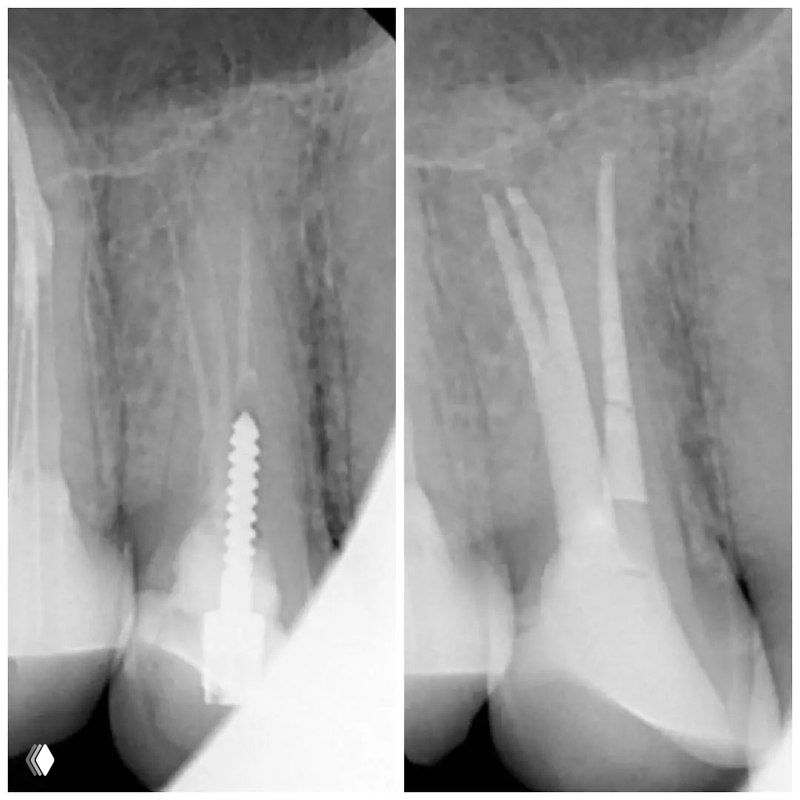

Распространенность: 1 премоляр вч - 3.2%, 2 премоляр вч - 0.4%

На что обратить внимание:

- классическую овальную полость доступа нужно немного расширить в области щёчных каналов в мезио-дистальном направлении

- проводить аккуратное расширение щёчных каналов, так как в области данных корней очень мало дентина (в моём случае расширение 25.04)

- аккуратно латералить без лишнего давления, а для вертикалки использовать самые тонкие плаггеры. А в идеале сделать гибрид.